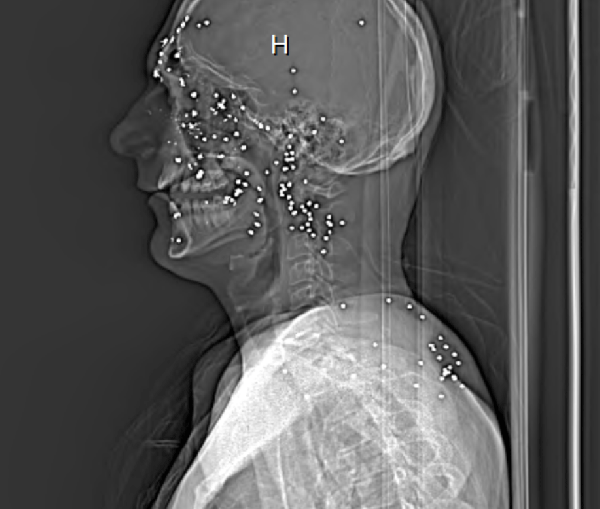

“My dental X-ray showed 53 pellets in it,” Barrett said. “It’s unbelievable how many pellets I have in my face, and I’m not dead.”

“My left eye socket was broken, my left cheekbone was broken, my nose was broken and I have what looks like acne scars where the pellets raged trough the side of my face,” he said. “One pellet hit ¼-inch from my carotid artery, and one went into my brain through my sinus cavity.”

His CT scan still shows between 90 and 110 pellets lodged under his skin. Doctors are trying their best to see if he will ever gain any usable vision in his right eye.